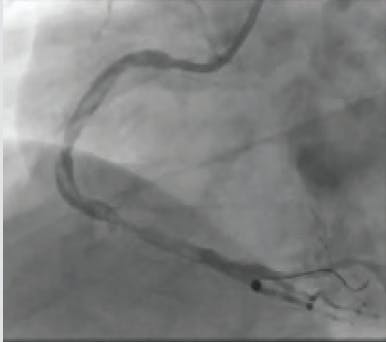

A 2-mm balloon was used to perform the Dotter technique to predilate the vessel (Figure 1). Heavy thrombus burden was visualized angiographically, and it was decided that mechanical thrombectomy with CAT RX would be introduced (Figure 2). After multiple passes of CAT RX with 30 seconds of aspiration each, there was improved flow through the vessel (Figure 3). Then, 4- X 38-mm and 4- X 32-mm drug-eluting stents (DESs) were placed distally and in the midbody, resulting in thrombolysis in myocardial infarction (TIMI) 3 flow (Figure 4).

Figure 1. An angiogram shows an occluded right coronary artery (RCA).

Figure 2. Heavy thrombus burden was visualized angiographically after using the Dotter technique.